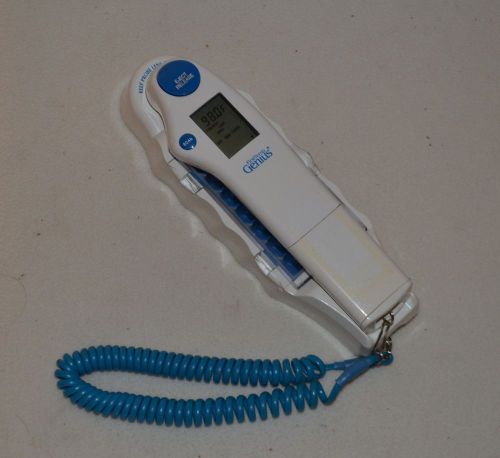

First Temp Genius Temperature Infrared Tympanic Thermometer Model 3000A 3000-A